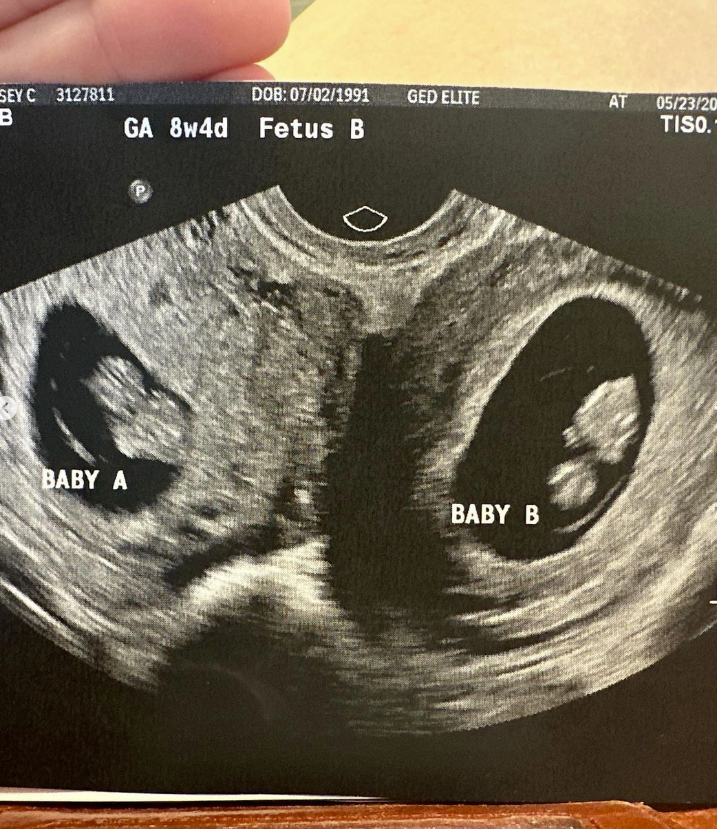

Screenshot des zur Verfügung gestellten Ultraschallbildes ©doubleuhatchlings, Kelsey Hatcher

Kategorisierung der Schwangerschaft

Die Einzigartigkeit von Hatchers Situation stellt die Ärzte vor die Herausforderung, wie sie die beiden Schwangerschaften kategorisieren sollen. Jedes Baby hat seine eigene Plazenta, und aus medizinischer Sicht wird dieser Fall als so selten betrachtet, dass die Ärzte weiterhin von Zwillingen sprechen, obwohl es vergleichbar mit zweieiigen Zwillingen ist.